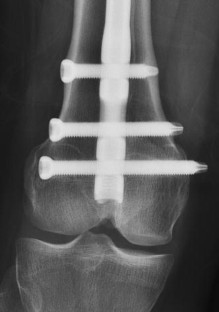

Fig. 1